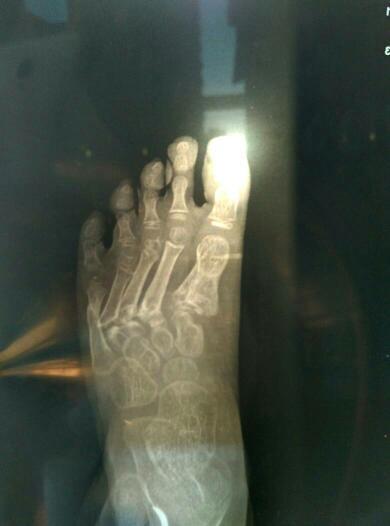

先天性第四跖骨短小症

右脚第五跖骨基底部骨折小记

四岁小孩因为车祸导致右脚跖骨1-5粉碎性骨折,目前已经七个月,小拇指